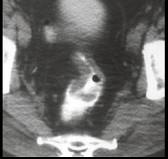

问题 男,53岁,便秘、血便,大便变细,CT如图,应考虑为 ( )

选项 A.肠Crohn病 B.直肠结核 C.溃疡型直肠癌 D.慢性溃疡性结肠炎 E.直肠淋巴瘤

答案 C